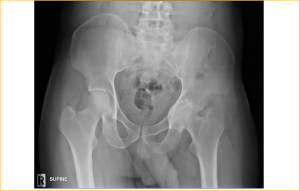

A segmental fracture of RT Femur in a 63 year old lady!